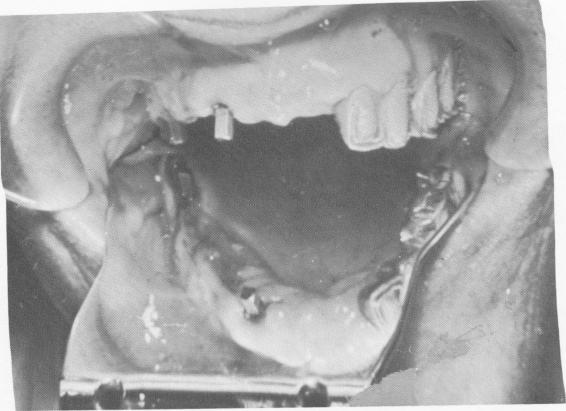

be removed first. This unique situation provided another opportunity for obtaining a human bone block specimen.

According to the lateral plate (Fig. 4-28), the two implants in the tuberosity were solid. However, only one was successfully removed with the bone still attached. The implant directly underneath the crown portion of the impacted cuspid was loose and bone loss evident (Fig. 4-29); it was removed with connective tissue attached. The tuberosity implant with bone attached and the failing implant were

submitted for examination (Fig. 4-30). The specimens were sectioned and photomicrographs taken (Fig. 4-31).